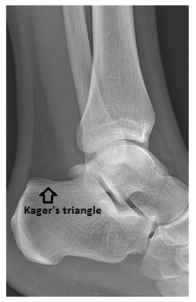

Sur une radiographie de profil de la cheville, comment s’appelle la poche de graisse en avant du tendon d’Achille ?

Le triangle de KAGER

Comment s’appelle la graisse sous le ligament rotulien ?

Bourse de Hoffa